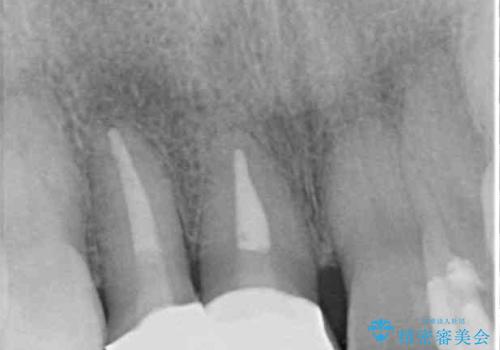

お粗末な根管治療、根管充填がされていたため、補綴治療を行うにあたり根管治療を行いました。